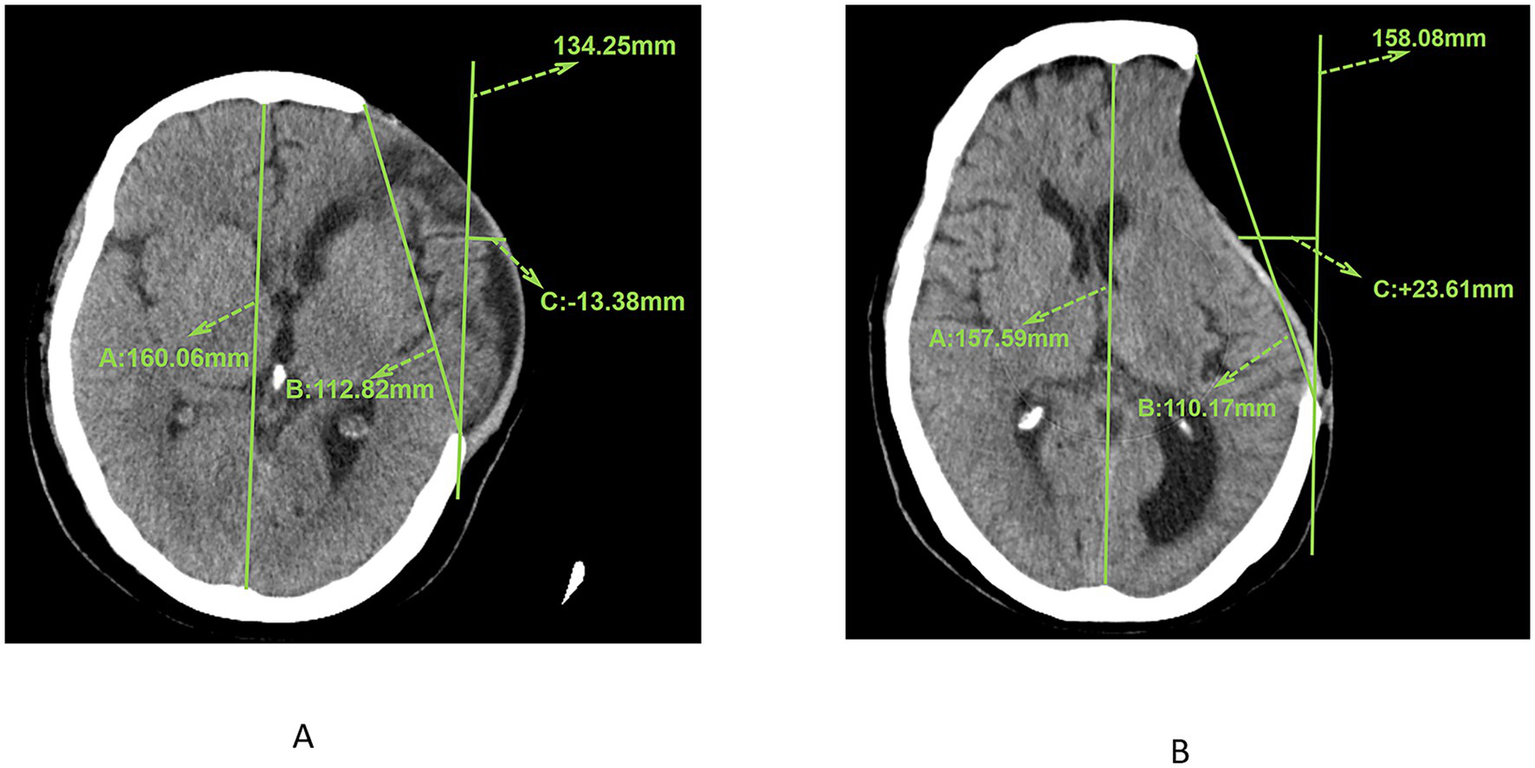

The measurement of skin flap shift was conducted at the image plane that exhibited the most pronounced deviation. All images employed for the measurement of skin flap shift were obtained 7 days prior to surgery and measured by two associate chief physicians, with excellent inter-observer reliability indicated by an intraclass correlation coefficient (ICC) of 0.923 (95% CI: 0.894–0.945, p < 0.001). Initially, the bony platform at the cranial defect site that was furthest horizontally from the midline was selected. A straight line parallel to the midline reference line was drawn from the centre of the defect margin. The skin flap shift was determined by measuring the distance between this line and the flap position at the midpoint of the craniectomy axis. In instances where the flap measurement point did not reach this vertical line (Figure 2A, +23.61 mm), it was deemed positive. Conversely, if the flap measurement point lay lateral to the reference line (Figure 2B, −13.38 mm), it was negative. Cerebral displacement was the underlying factor that resulted in the non-utilisation of the contralateral side as a reference benchmark.

Figure 2

(A) CT image showing the measurement results of the maximum axial craniectomy size (110.17 mm) and skin flap shift (23.61 mm). (B) CT image showing the measurement results of the maximum axial craniectomy size (112.82 mm) and skin flap shift (13.38 mm).